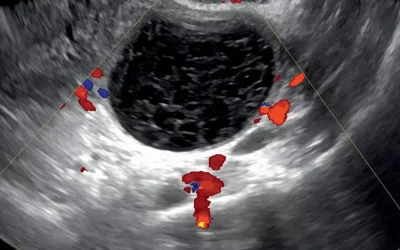

کیست تخمدان  کیست یک تومور پر مایع است که در تخمدان رخ می دهد. تخمدان، دو اندام کوچک در بدن خانم ها است، و در هر دو طرف رحم قرار گرفته است.  تخمدان ها هورمون های...